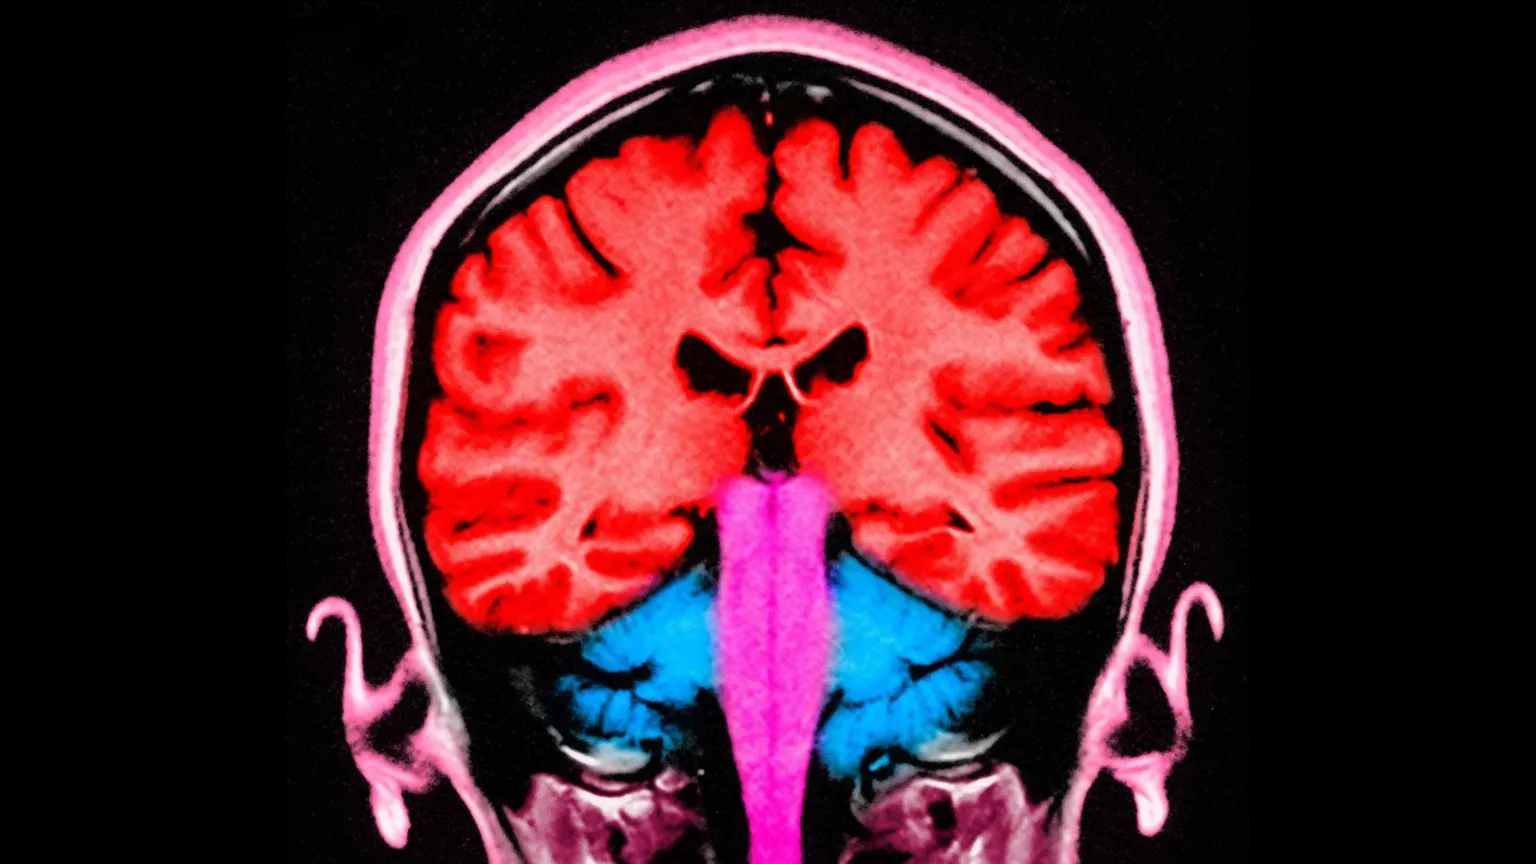

During the experiment, an electrical current was applied to the frontal and parietal areas of the brain – situated at the front and towards the back. When these areas were stimulated at the same time, the participants gave away more money.

In that study, the researchers pinpointed the two brain areas that appeared to be “talking to each other” – with brain cells firing at the same frequency – when players gave away more money.

Those two brain areas are known to play a role in decision-making and in empathy, or distinguishing the feelings of others from our own.

When a more selfless decision was made, the empathy region and the decision region appeared to communicate.